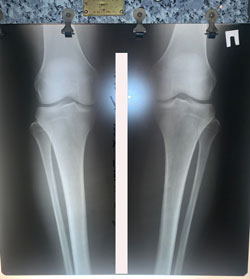

Исходник - 36 лет.

Дата операции - 02.12.2020

Ещё раз: невозможно устранить варусную деформацию при помощи круропластики

Очередной пример!